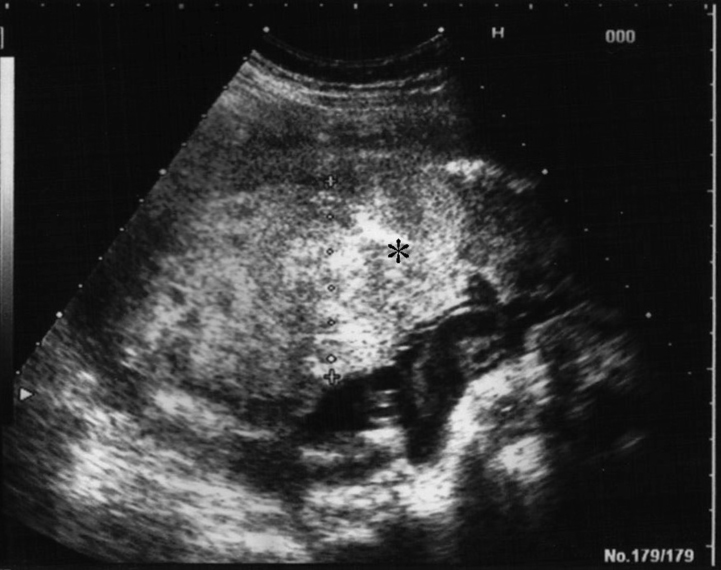

超音波所見

胎盤は55mmに肥厚しており、アスタリスク(*)で示す高エコー領域の部分が血腫である。

出典

img

1: 著者提供